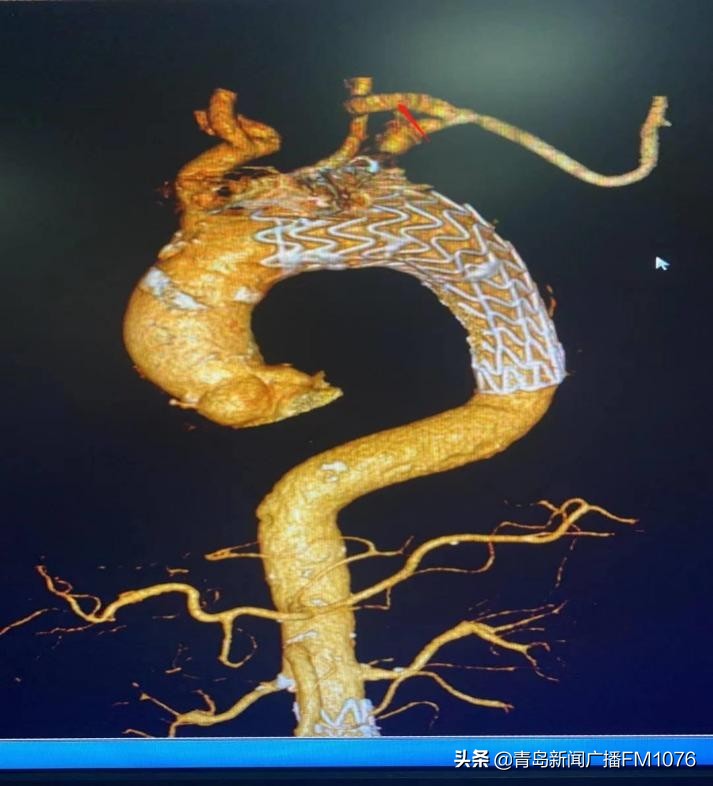

手术先进行左颈总动脉-左锁骨下动脉人工血管转流术,保证脑部和上肢的血液供应。后于采用微创介入手术方式,于右股动脉穿刺入路行主动脉弓动脉瘤腔内隔绝术,术中造影见转瘤人工血管血流通畅,主动脉弓动脉瘤封堵良好,未见内漏。既保证了脑部及上肢的血供,又完全腔内隔绝了主动脉弓动脉瘤,从而保证肿瘤不会破裂和生长,安全解除了患者体内的“定时*弹炸**”。杂交手术历时3.5小时成功完成,术后一天,患者恢复良好转回普通病房,目前已康复出院。

转流人工血管

红色箭头为转流人工血管